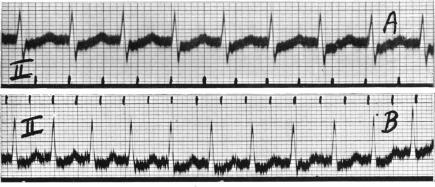

Campbell M, Elliott G A

Cardiographic Department, Guy's Hospital, and the National Hospital for Diseases of the Heart.

Br Heart J. 1939 Apr;1(2):123-60. doi: 10.1136/hrt.1.2.123.